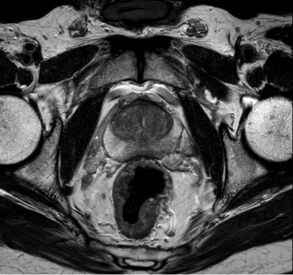

Recently, there have been a lot of advances in prostate cancer diagnosis. For men with elevated PSA, a MRI scan can be arranged to look for any tumours or suspicious lesions within the prostate gland. The MRI images can be fused into the ultrasound image during prostate biopsy, and targeted biopsy of the prostatic tumour can be performed. This will increase the accuracy of the biopsy procedure. On the other hand, if the MRI scan shows a completely normal prostate gland, prostate biopsy may also be safely avoided.